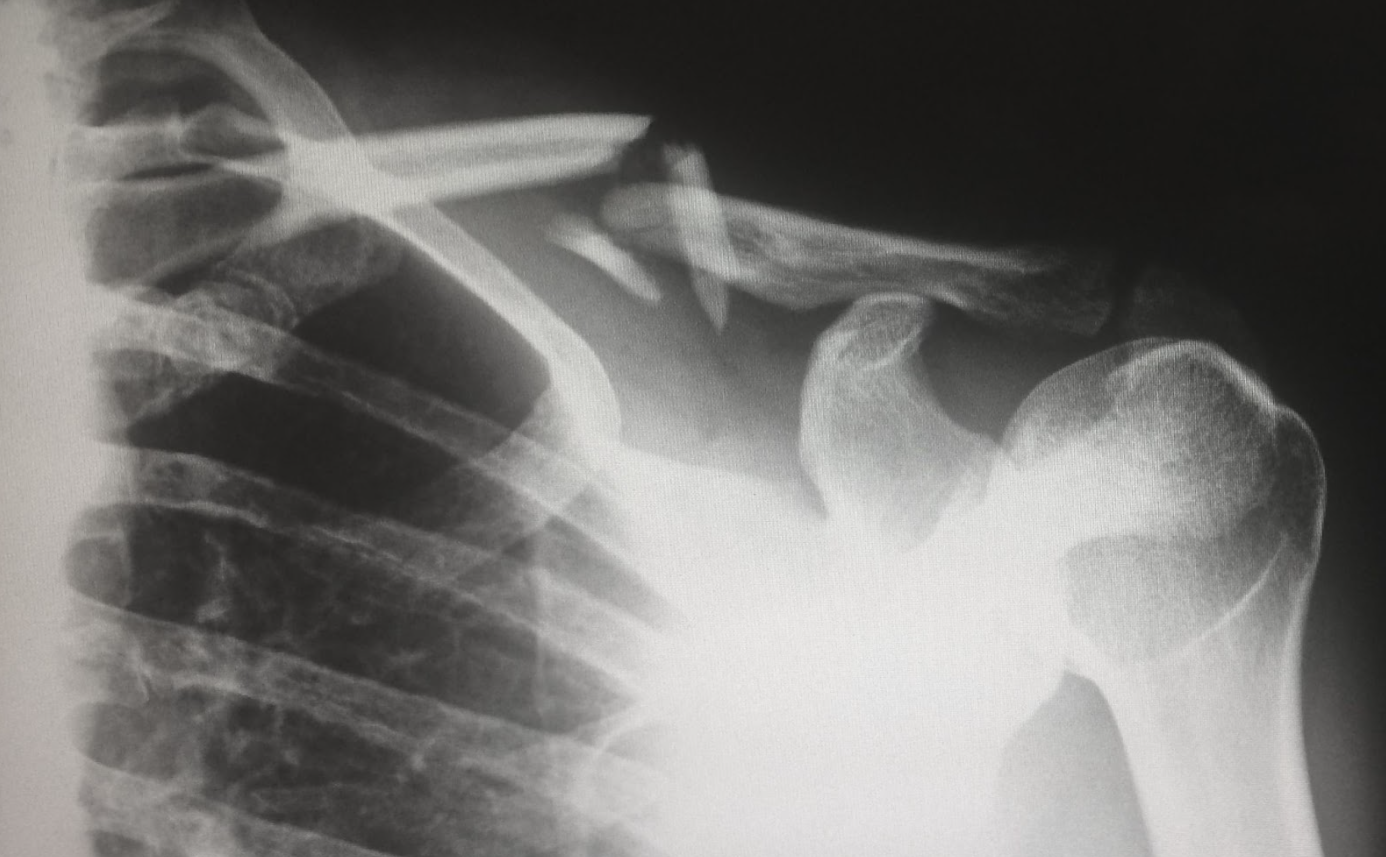

UMĂR

Tratament ortopedic, chirurgia reconstructivă a umărului, protezare sau artroscopie de umăr: reinserție tendoane coafa rotatorilor, stabilizare umăr dislocat, transferuri tendinoase.